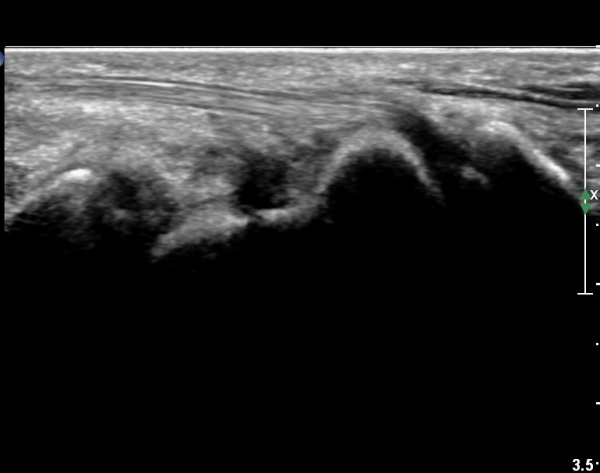

¼Õ¸ñ ÀåÃø ÁÖ»ó°ñ Á¾´Ü¸é °Ë»ç¿¡¼ ¹Ì¼¼ÇÑ ÁÖ»ó°ñ ÇÇÁú°ñ ¿¬¼Ó¼º ¼Ò½Ç(loss of cortical bone continuity)ÀÌ °üÂûµÊ(»çÁø 1, 2).

È®ÁøÀ» À§ÇÑ ÃÊÀ½ÆÄ°Ë»ç¿¡¼ ÁÖ»ó°ñ °ñÀý È®ÀÓ µÊ.